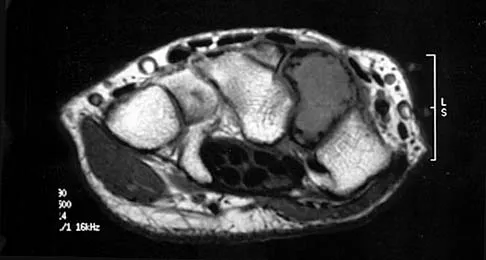

Figures 34a through 34c show an axial proton density (spin echo long TR, short TE) image, a sagittal inversion recovery (STIR) image, and a sagittal T1-weighted (short TR, short TE) image of the left thigh. What is the most likely diagnosis?

Explanation

The images reveal a region of increased signal within the rectus femoris muscle with mild, ill-defined surrounding edema. The presence of high intensity signal on the T1-weighted image favors acute blood, in this case associated with a rectus femoris muscle tear or fatty tissue. However, because of fat suppression, a fatty lesion or lipoma would be dark on STIR, rather than bright as in this image. Most foreign bodies are low intensity signal and if small, are difficult to evaluate with MRI. The lack of adjacent subcutaneous soft-tissue edema or surrounding fluid makes pyomyositis an unlikely diagnosis.